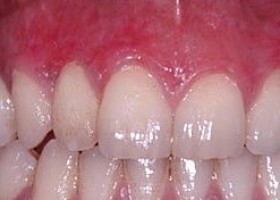

Periodontics is that specialty of dentistry which encompasses the prevention, diagnosis and treatment of diseases of the supporting and surrounding tissues of the teeth or their substitutes and the maintenance of the health, function and esthetics of these structures and tissues.

More advanced cases of gum disease are treated by surgery performed by a dentist or periodontist (a specialist that treats diseases of the gums and supporting structures of the teeth). The following surgical procedures are used, depending on the severity of the disease:

One of the leading cause of gum disease is poor dental hygiene habits. By actively cleaning your teeth, flossing between your teeth and stimulating your gums, you can take better care of your teeth and gums (the Skin of Your Teeth) every day: